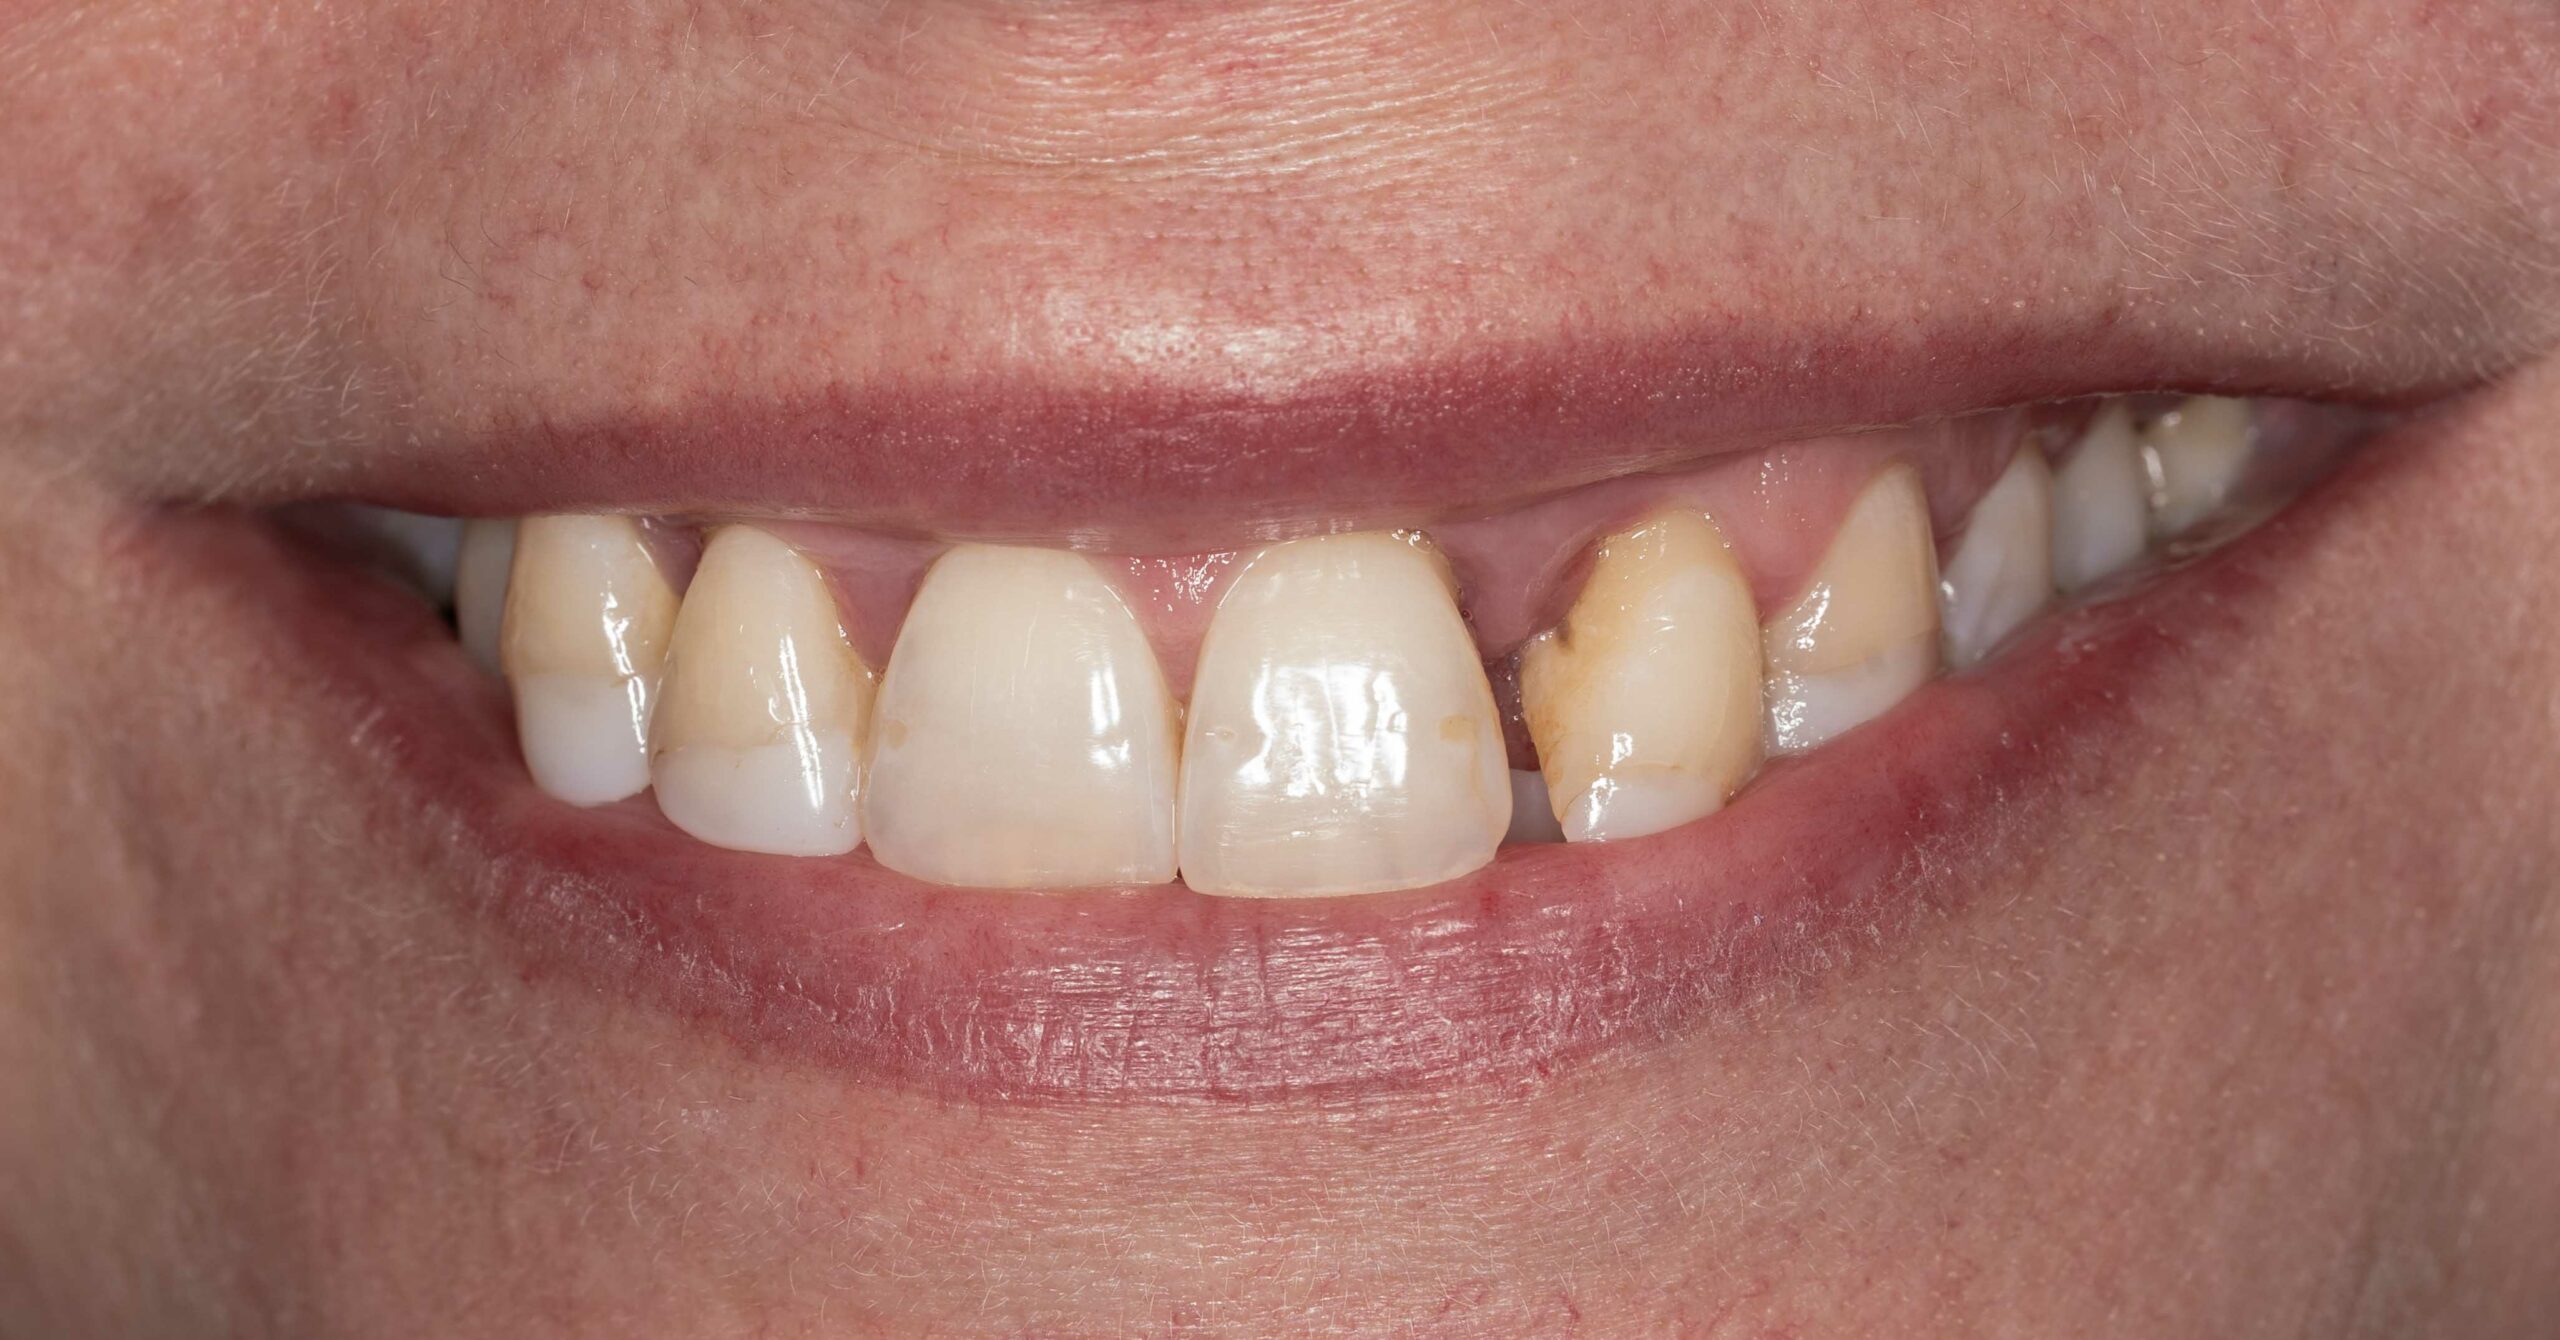

utrata zęba po urazie

Nasi pacjenci mogą liczyć na niezwłoczną oraz profesjonalna pomoc w każdej, nawet najbardziej stresującej sytuacji. Młoda pacjentka zgłosiła się z powodu utraty zębów przednich, do czego doszło kilka dni wcześnej, w wyniku potracenia przez kierowce elektrycznej hulajnogi. Leczenie polegato na niezwtocznym wprowadzeniu implantów zebowych oraz tymczasowej odbudowie zebów, dzieki czemu pacjentka jeszcze tego samego dnia odzyskata peten usmiech. Wprowadzenie implantów w odcinku przednim stanowi niezwykte wyzwanie. Aby osiagnac naturalny wyglad oraz wysoka estetyke czesto wymaga dodatkowych zabiegów regeneracyjnych na okolicznych tkankach miekkich oraz twardych. Przedstawiony efekt to uśmiech po wykonaniu ostatecznej odbudowy protetycznej.